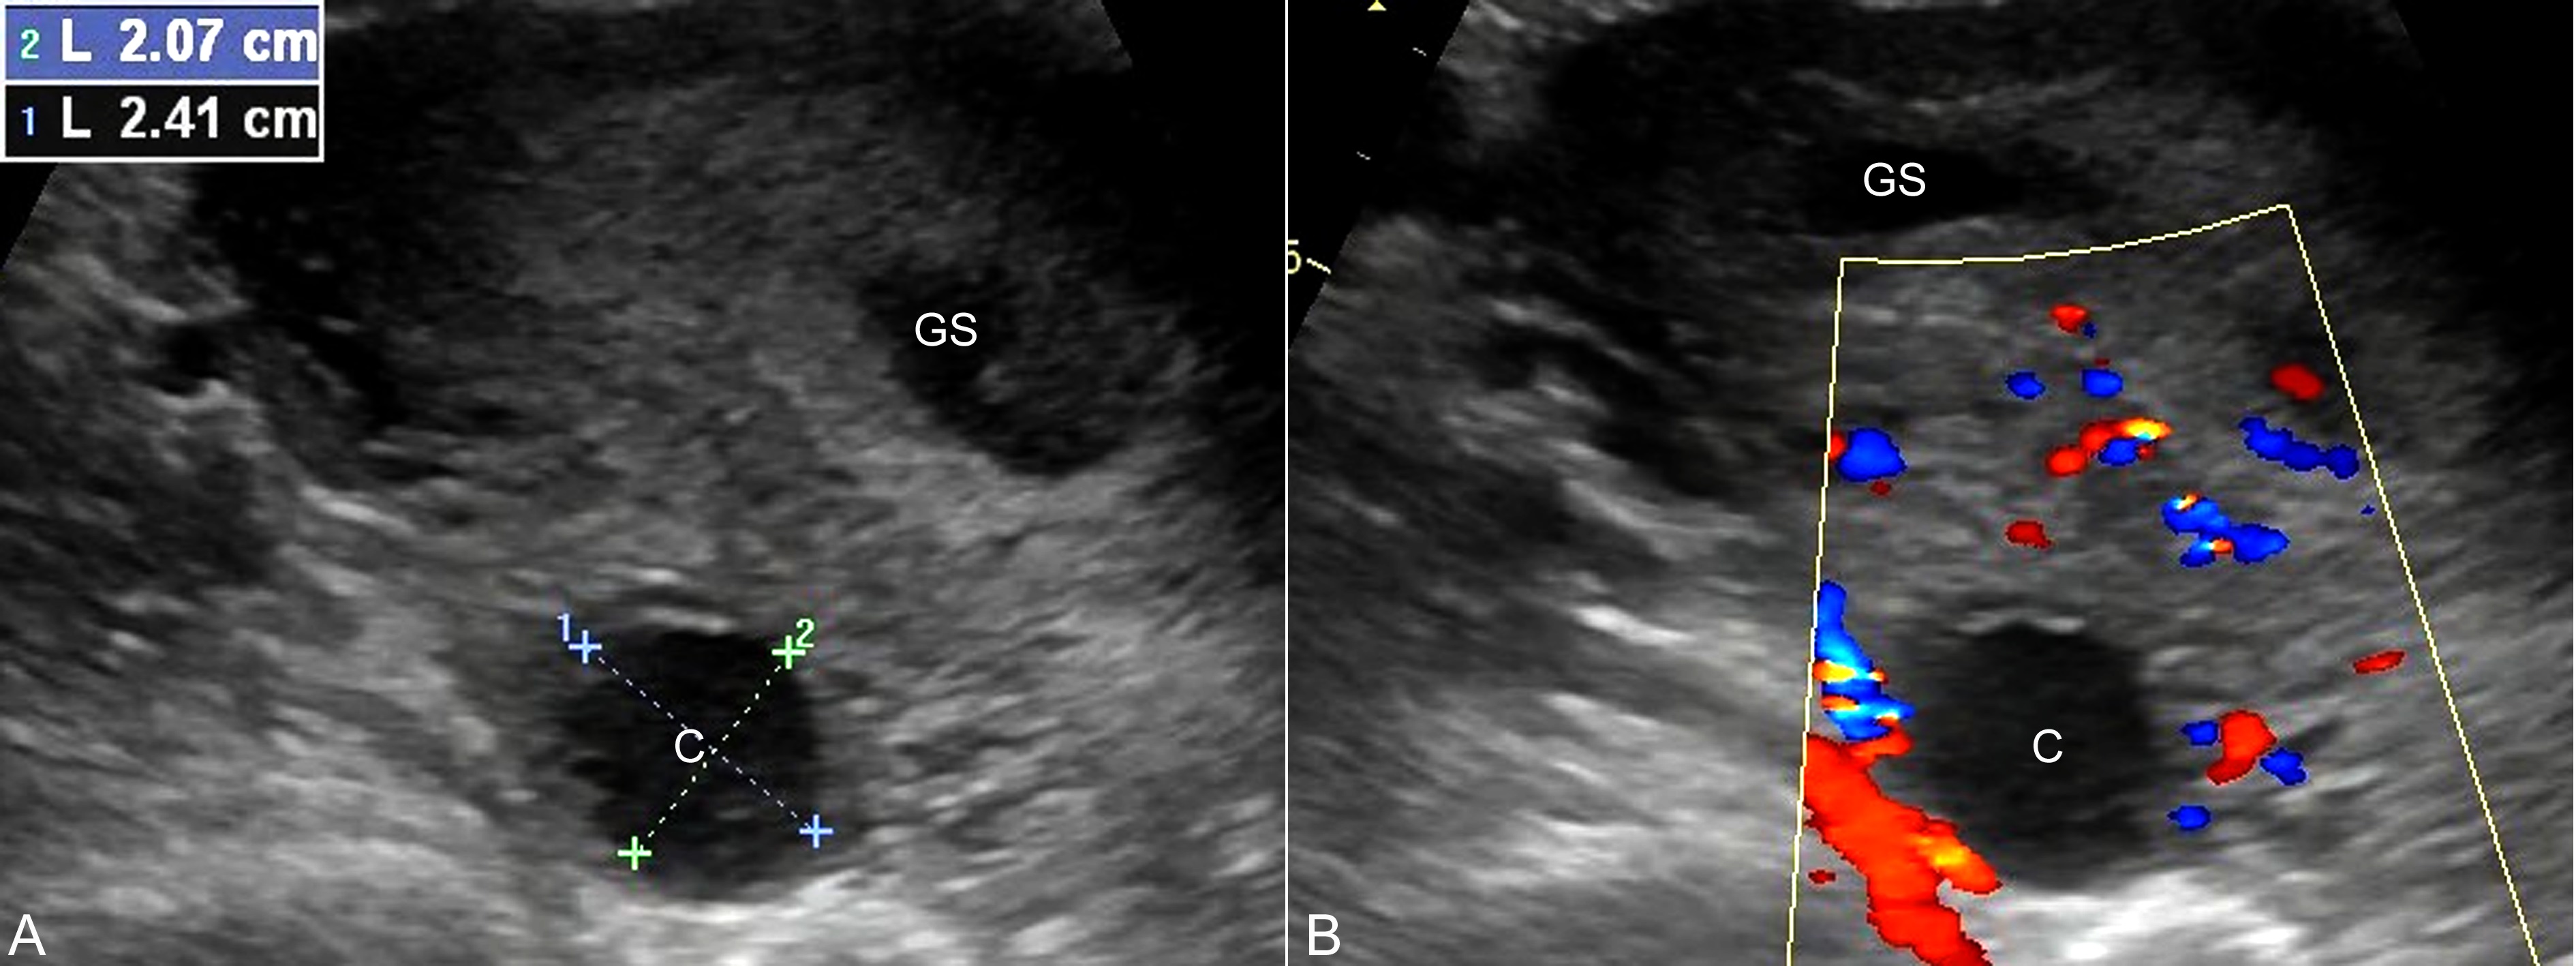

黄体囊肿(corpus luteum cyst)是妊娠期最常见的卵巢瘤样病变,可占卵巢局限性病变的14.2%。受精卵植入24小时以后,滋养层细胞分泌的绒毛膜促性腺激素刺激黄体形成妊娠黄体(corpus luteum of pregnancy)。在妊娠前10周内,妊娠黄体是孕妇体内孕激素和雌激素的主要产生部位,对促进子宫内膜蜕膜化和维持妊娠的正常进行有重要作用。此后,妊娠黄体的功能逐渐由胎盘代替,几乎均在妊娠第16周~18周以后消退。典型的妊娠黄体超声显像检查显示为附件区的无回声区,直径2cm~3cm,壁显示稍厚,内部为单房性,并可合并有少量点状低回声,此种回声多数无病理意义,几乎均在产前检查中偶然发现。如果妊娠黄体不消退,或持续增大,内部囊腔扩大,可形成黄体囊肿。超声显像检查显示囊肿直径多在4cm~6cm之间,形态规则,边缘清晰,壁较厚,但均匀一致(图1);内部多显示为无回声区,有时可见纤细的分隔回声;如果合并囊内出血,可以在囊腔无回声区内显示较粗的点状低回声,分布均匀或不均匀(图2A),CDFI检查周围血流稍增多或显示环状血流(图2B)。多数黄体囊肿较小,个别情况下囊肿可相当大,偶尔可以超过10cm;部分囊肿可以不消退,甚者维持到妊娠晚期,直至分娩。

图1早孕并黄体囊肿声像图:C:黄体囊肿;GS:孕囊